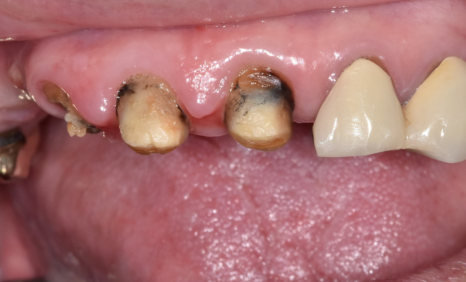

위쪽 앞니 5개는 상황이 달랐습니다.

여러 개가 하나의 보철(브리지)로 묶여 있었는데,

이를 제거해 보니

230715

안쪽 치아들은 많이 상해 있었고 남아 있는 치아 자체도 너무 작았습니다.

이 상태로 다시 씌운다고 해도

보철이 오래 버티기 어려운 상태였습니다.

이 경우에는

무리해서 약한 치아를 붙잡고 가기보다는,

장기적으로 버텨 줄 수 있는 임플란트로 진행하는 것이 더 안전합니다.

환자분께 충분한 설명 후,

위의 앞니를 포함하여 나머지 상태가 좋지 않은

치아들은 임플란트로 진행하기로 하였습니다.